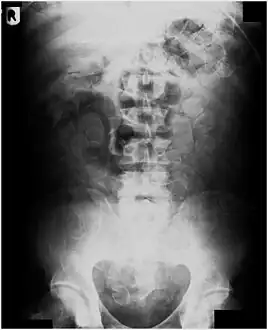

Abdominal X-ray showing small packages of cocaine swallowed by a trafficker.

Vibrator stuck in the rectum can be seen on this abdominal X-ray.